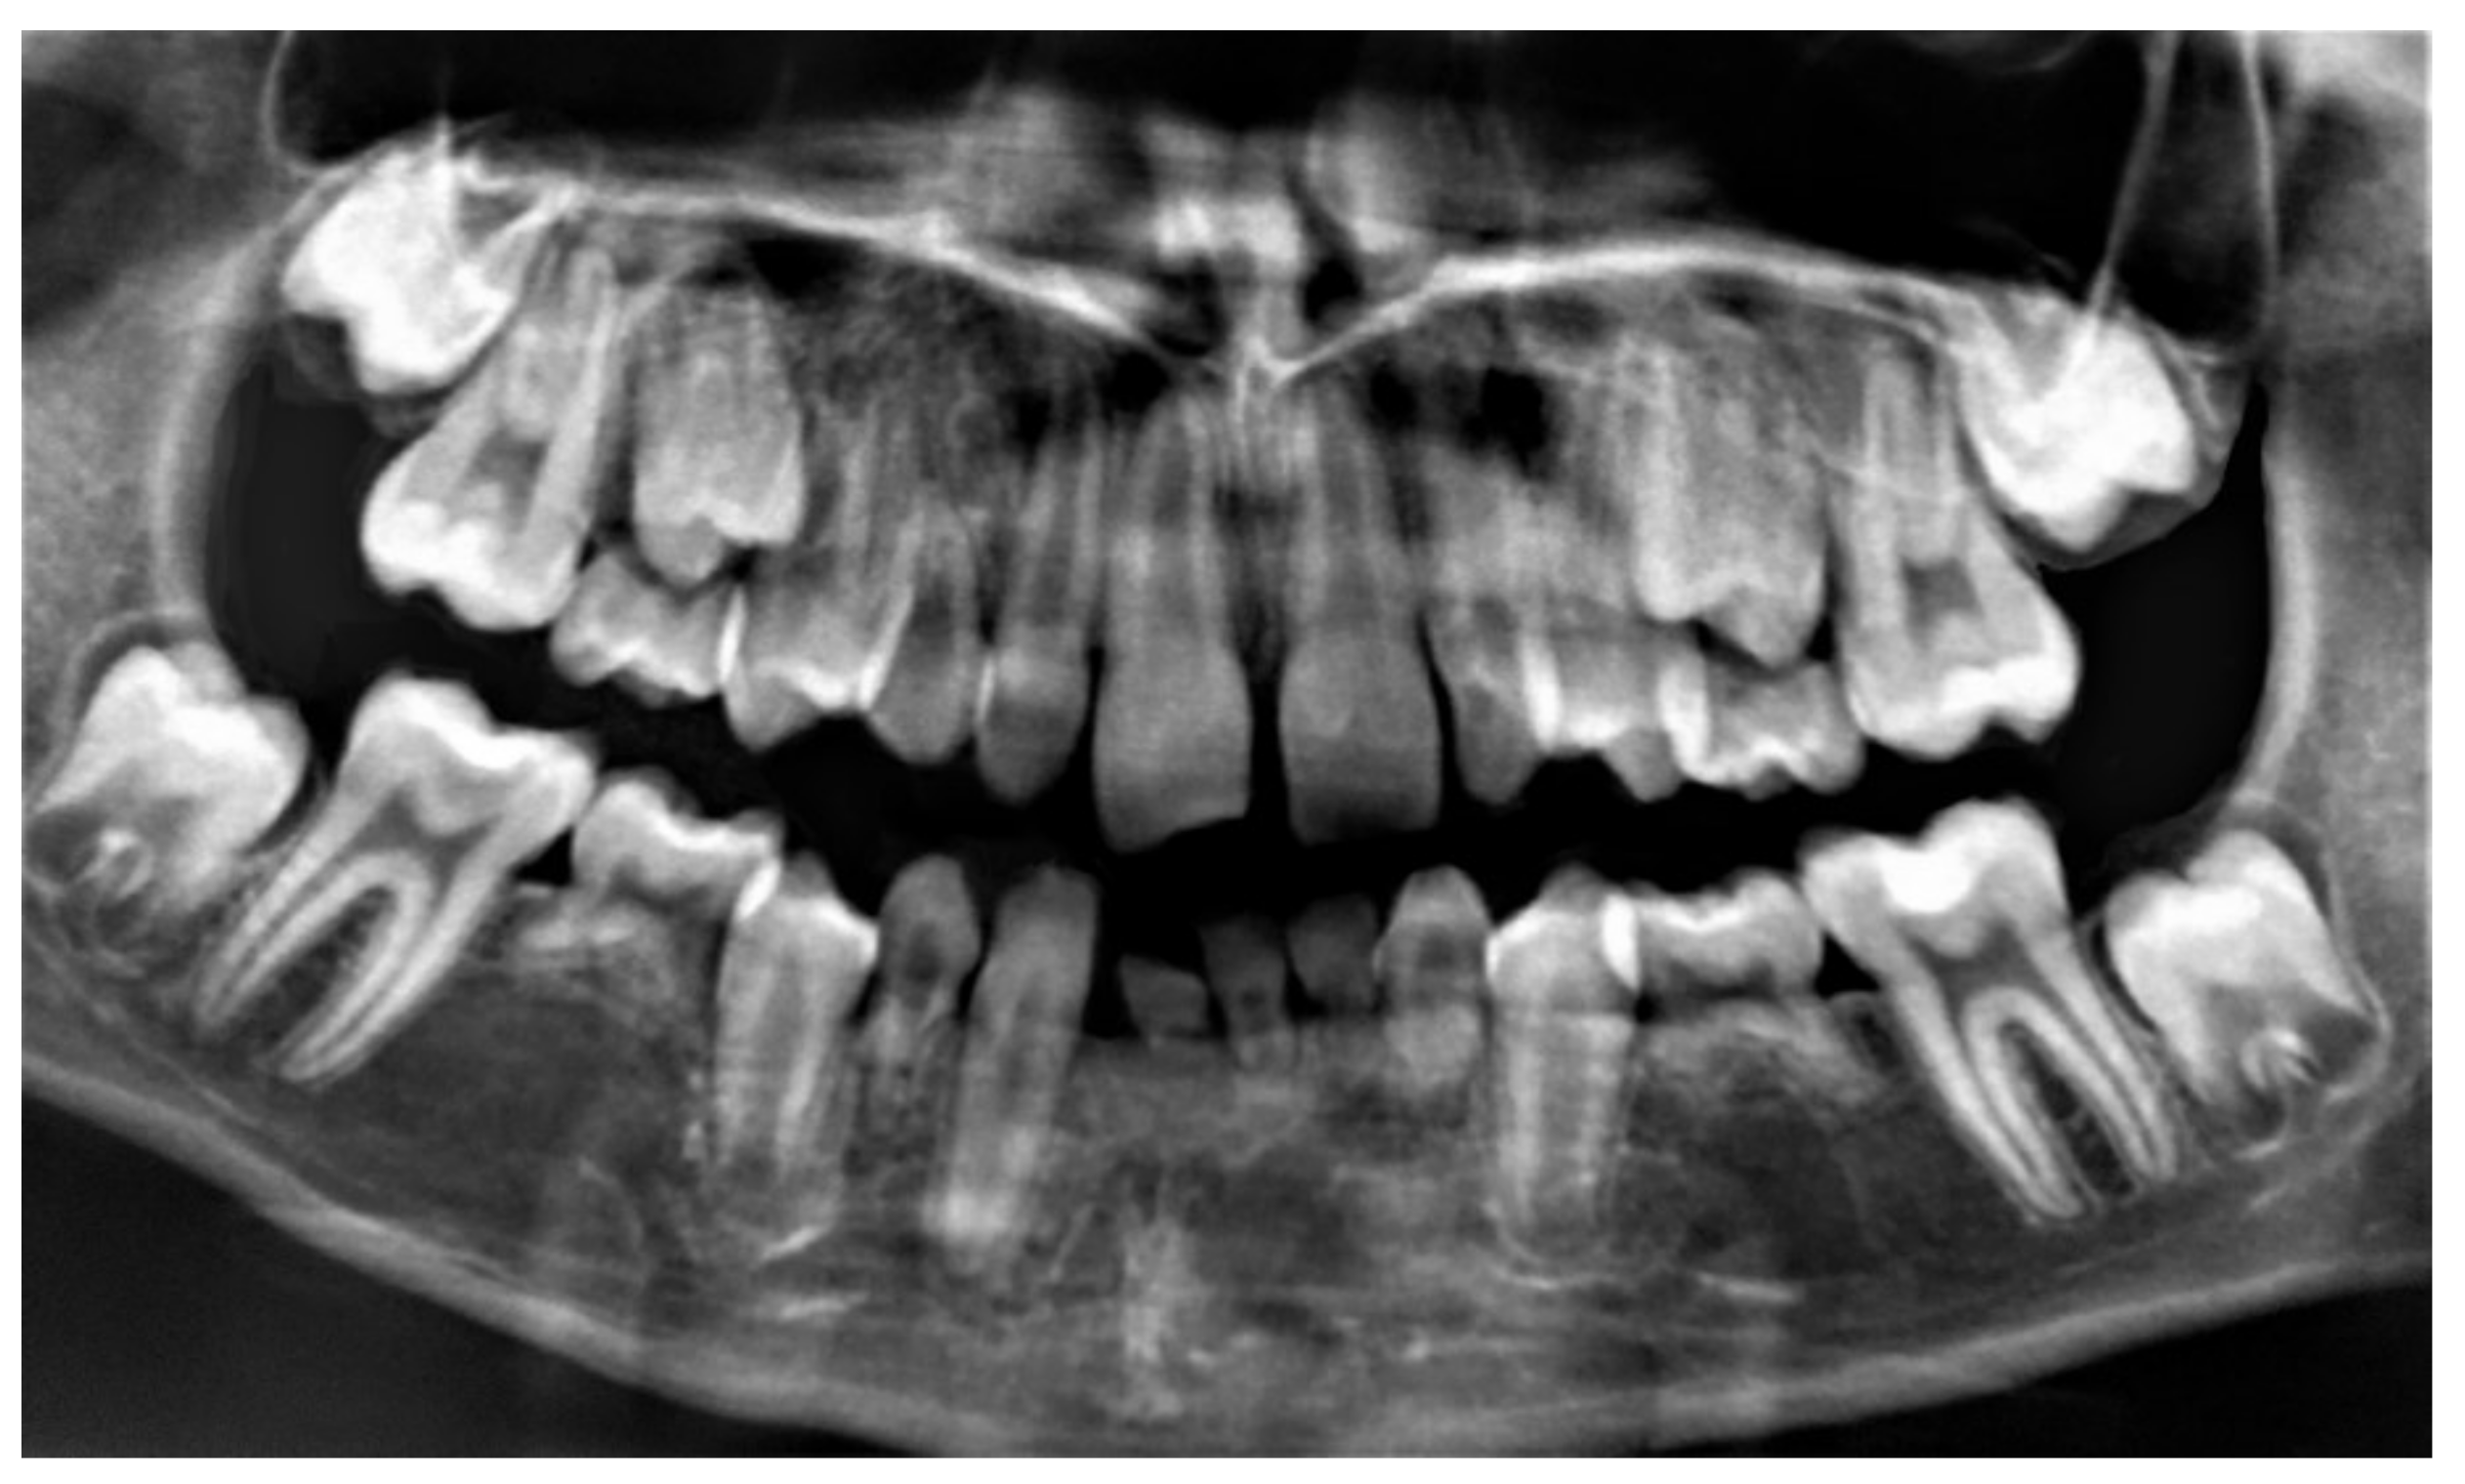

3.1. Clinical and Radiological Oral Examination

| Upper Teeth n (%) | Lower Teeth n (%) | |||

|---|---|---|---|---|

| Temporary teeth n = 18 | Lateral incisor | 2 (11.1) | Lateral incisor | - |

| Second molar | 8 (44.4) | Second molar | 8 (44.4) | |

| Definitive teeth n = 47 | Central incisor | - | Central incisor | 2 (4.2) |

| Lateral incisor | 8 (17.0) | Lateral incisor | 4 (8.5) | |

| Canine | - | Canine | 1 (2.1) | |

| First premolar | 5 (10.6) | First premolar | - | |

| Second premolar | 12 (25.5) | Second premolar | 7 (14.9) | |

| First molar | 1 (2.1) | First molar | - | |

| Second molar | 2 (4.2) | Second molar | 5 (10.6) | |

| Sagittal Plane n = 15 | Transverse Plane n = 15 | Vertical Plane n = 15 | |||

|---|---|---|---|---|---|

| n (%) | n (%) | n (%) | |||

| Class I | 4 (26.6) | Normal occlusion | 5 (33.3) | Normal occlusion | 6 (40.0) |

| Class II | 9 (60.0) | Crossbite | 5 (33.3) | Overbite | 7 (46.6) |

| Class III | 2 (13.3) | Scissor bite | 3 (20.0) | Open bite | 2 (13.3) |

| Overjet | 4 (26.6) | ||||

| Anterior crossbite | 3 (20.0) | ||||